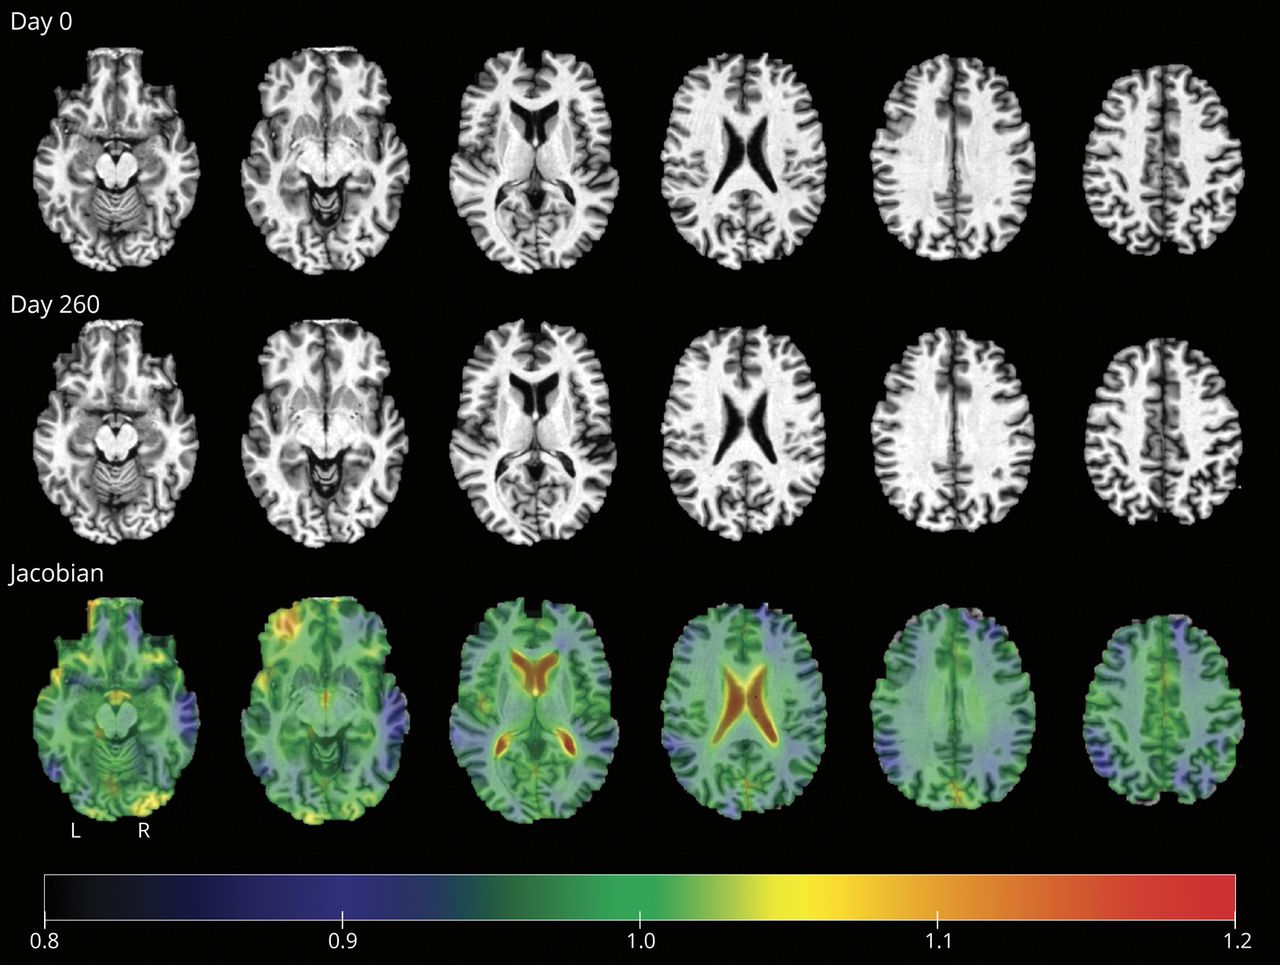

对于纵向分析,我们量化了每个ROI中的变化。对于每个个体,我们使用DiffeoMap46为了使后期扫描与早期扫描对齐,使用自动图像配准,然后进行大变形微分胚度量映射。雅可比行列式是大变形微分胚度量映射变形场的局部展开因子,用于量化体素水平的局部体积变化。小于1的雅可比矩阵表示相对于早期扫描的收缩,而大于1的雅可比矩阵表示扩张。我们计算了横截面分析中使用的22个roi中的每一个的平均雅可比矩阵,使用早期扫描的分割来定义区域。图1给出了一个雅可比行列式映射的例子。我们计算了横截面分析中使用的22个roi中的每一个的平均雅可比矩阵,使用早期扫描的分割来定义区域。

在横断面分析中,粉红色区域表示较小的容量与BNT上较差的命名性能相关的区域;在两个时间点都确定了相同的roi。在纵向分析中,绿色区域表示体积减少(即萎缩更多)与命名性能下降更大相关的区域。缩写:BNT =波士顿命名测验;ROI =感兴趣的区域。